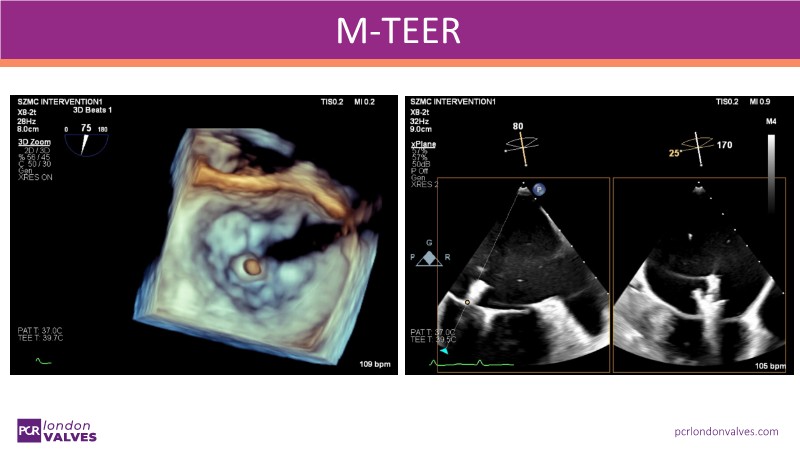

This LIVE case symposium brings mitral regurgitation guidelines into real clinical practice. Through step-by-step patient demonstrations and insightful discussion, the session explores how recommendations guide decision-making in ventricular and atrial secondary MR, how the heart team tailors therapy to individual anatomy and comorbidities, and how device iterations and procedural workflow can influence outcomes.

From medical optimisation to TEER selection and surgical considerations, the session highlights the reasoning behind each treatment choice. Watch now to find out more!